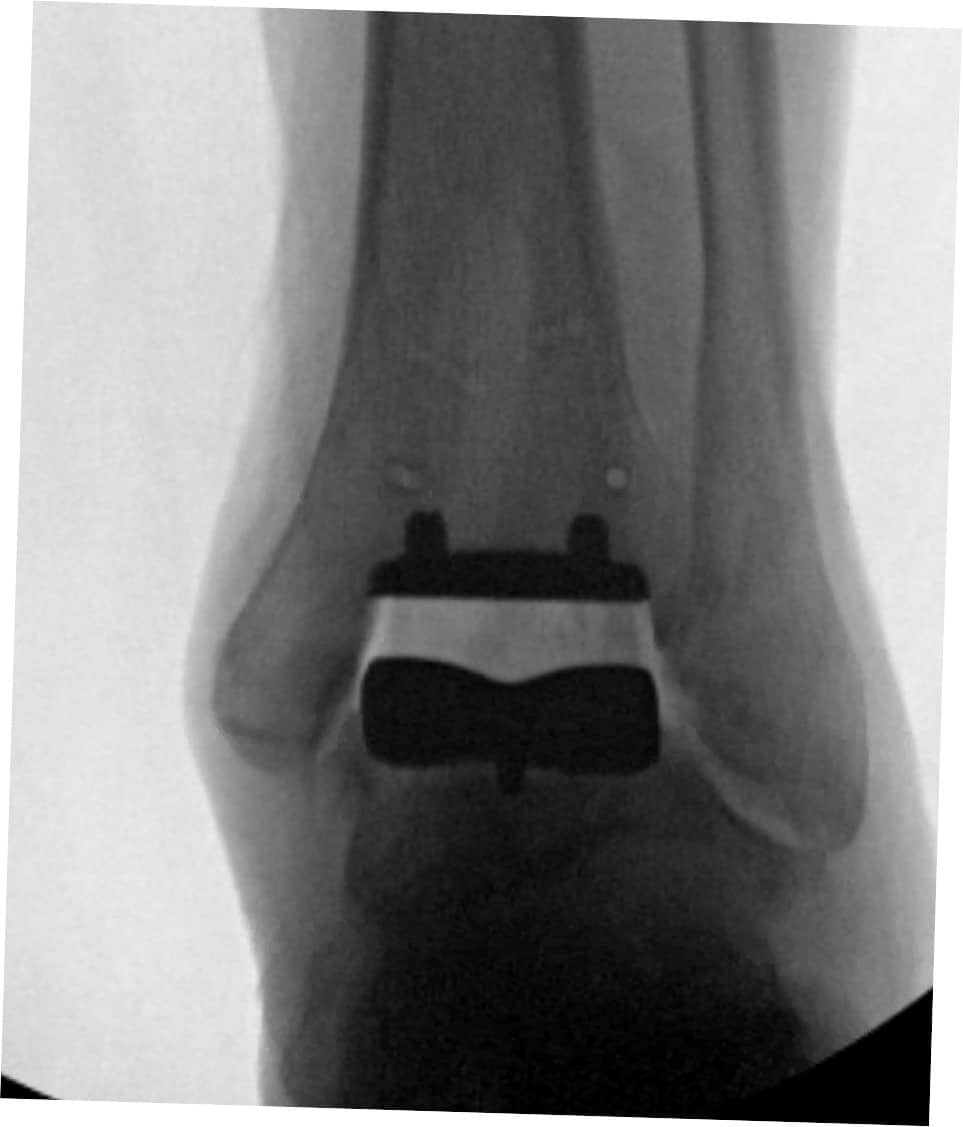

Join Paragon 28 for immersive cadaveric labs during ACFAS 2026 where you can work hands-on with two advanced total ankle systems. These focused sessions give podiatric surgeons the opportunity to explore technologies designed to improve outcomes for end stage ankle arthritis.